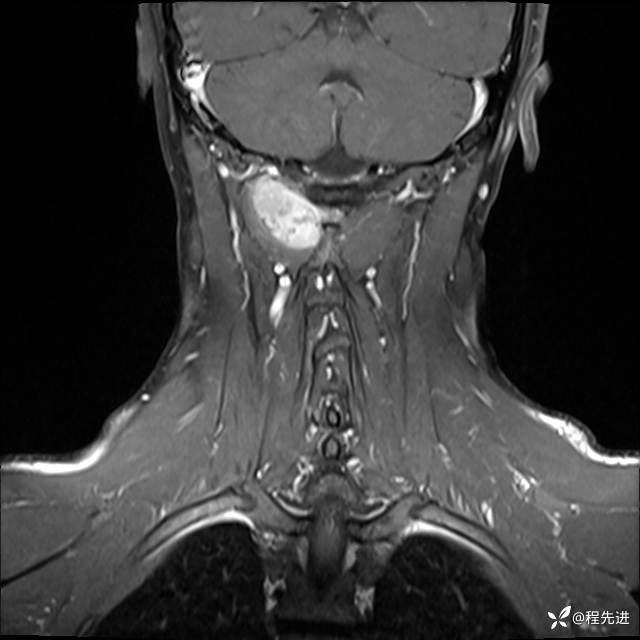

MRI平扫+增强:

T1增强: